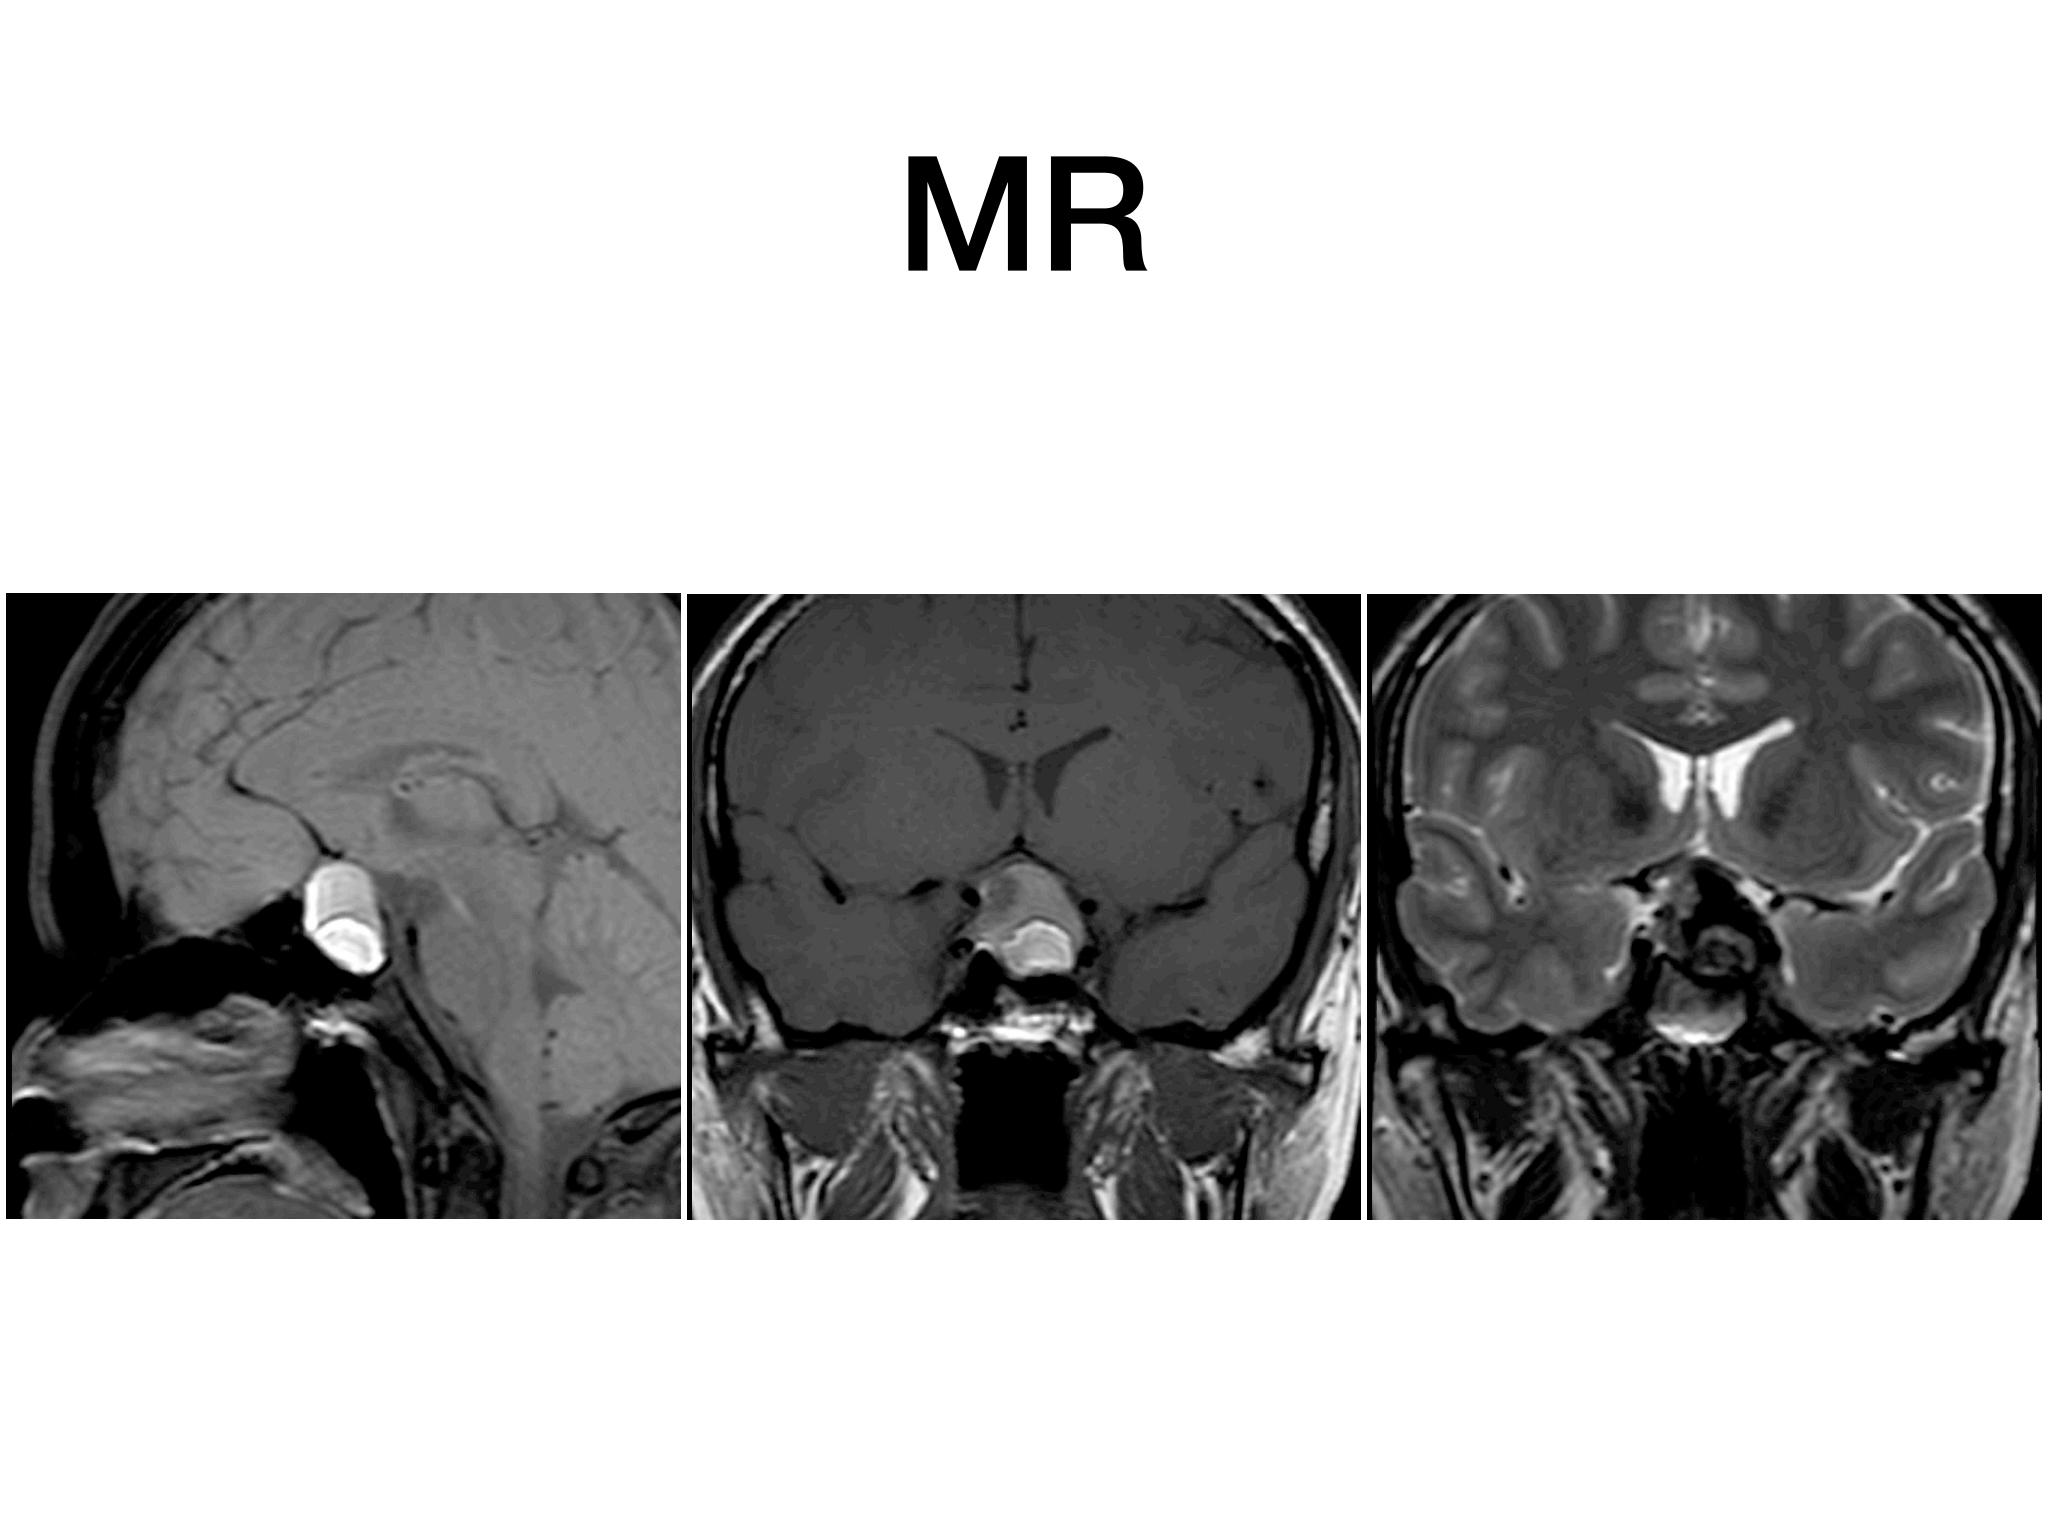

分享一例经鼻内镜泌乳素大腺瘤切除手术,患者青年男性,术前泌乳素>200ng/dl,MR提示大腺瘤合并瘤内出血,手术全切肿瘤,术后泌乳素降至正常,生化缓解,预后良好。